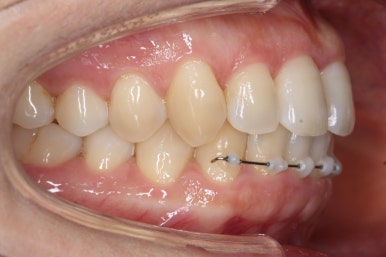

부산설측교정 키다리아저씨치과에서 장치를 부착한 이후의 모습입니다.

환자분은 교정장치가 보이는 것을 좋아하지 않으셔서 윗니는 부산설측교정 하는 콤비교정으로 진행했습니다.

콤비교정이란 윗니는 설측교정(안쪽으로 하는 교정), 아랫니는 바깥으로 하는 일반 교정을 조합해서(콤비)하는 교정치료를 뜻합니다.

사용한 장치는 부분교정에 특화 되어있는 부피가 작고 눈에 잘 띄지 않는 MTA라는 장치를 이용하였습니다.